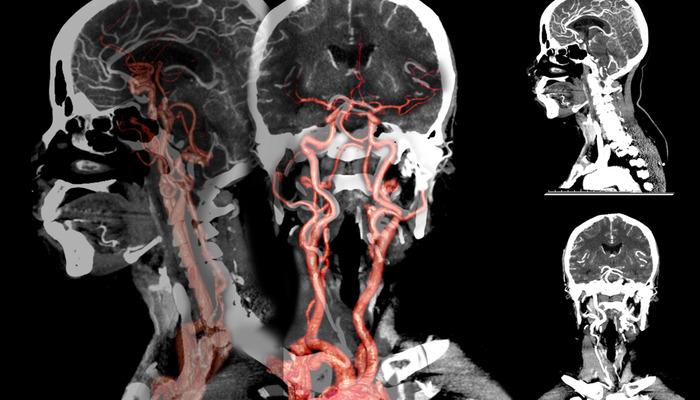

Doç. Dr., beyin kanamasının erkeklerde kadınlara göre daha sık görüldüğünü söyledi. Dr. Çakın, şunları söyledi: “Anevrizmal kanamalar, beyin atardamarlarındaki kabarcıklar nedeniyle meydana gelen beyin kanamaları olarak biliniyor. Özellikle sonbahar ve ilkbahar başlarında bu kanamaların yüzde 10 oranında arttığı gözlendi. Sigaranın etkisiyle beyindeki damarlar tıkanıyor.”

Doç. Dr., beyin kanamasında genetik hastalıkların etkili olabileceğini söyledi. Hakan Çakın, “Yüksek tansiyon, sigara kullanımı ve ileri yaşa bağlı olarak oluşan bu kabarcıklar, mevsimsel döngülerde daha çabuk ortaya çıkıp beyin kanamalarına neden oluyor. Genetik anevrizmalara da daha sık rastlanıyor. Çocukluk döneminde, özellikle Japonya ve Finlandiya’da, ancak “ülkemizde bu kadar yaygın değil. Belli bir yaştan sonra özellikle 30-50 yaş sonrasında hipertansiyon ve sigara kullanımının bu soruna büyük etkisi vardır. At nalı böbrek hastalığı, diyaliz hastalarında ya da tansiyon sorunları ve genetik bozukluklar genç yaşta görülen bireylerde dahi etkili olabiliyor” dedi.